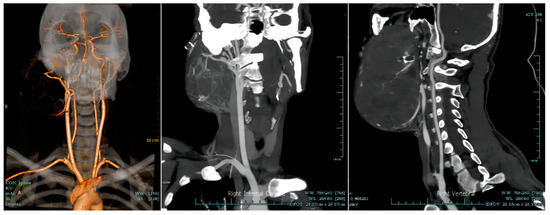

Giant Mandibular Ameloblastoma with Rare Hypercalcemia: A Case Report and Literature Review

by Wenyi Shen, Chenlu Xu, Pan Wang, Junpeng Chen, Dan Yu and Huiyong Zhu

Medicina 2023, 59(11), 1956; https://doi.org/10.3390/medicina59111956 - 6 Nov 2023

Ameloblastoma is the most common benign odontogenic tumor with local invasion and high recurrence, which generally occurs in the jaw bones. Hypercalcemia is a common paraneoplastic syndrome that is commonly observed in patients with malignancies but rarely encountered in patients with benign tumors. Thus far, not many cases of ameloblastoma with hypercalcemia have been reported, and the pathogenic mechanism has not been studied in depth. This paper presents a case report of a 26-year-old male diagnosed with giant ameloblastoma of the mandible, accompanied by rare hypercalcemia. Additionally, a review of the relevant literature is conducted. This patient initially underwent marsupialization, yet this treatment was not effective, which indicated that the selection of the appropriate operation is of prime importance for improving the prognosis of patients with ameloblastoma. The tumor not only failed to shrink but gradually increased in size, accompanied by multiple complications including hypercalcemia, renal dysfunction, anemia, and cachexia. Due to the contradiction between the necessity of tumor resection and the patient’s poor systemic condition, we implemented a multi-disciplinary team (MDT) meeting to better evaluate this patient’s condition and design an individualized treatment strategy. The patient subsequently received a variety of interventions to improve the general conditions until he could tolerate surgery, and finally underwent the successful resection of giant ameloblastoma and reconstruction with vascularized fibular flap. No tumor recurrence or distance metastasis was observed during 5 years of follow-up. Additionally, the absence of hypercalcemia recurrence was also noted. Full article

Show Figures

Figure 1